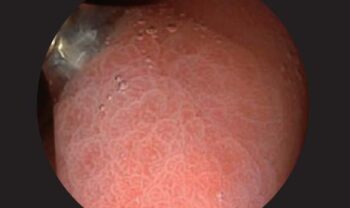

Өндөр нарийвчлалтай дүрс: 1080p HD нарийвчлалтай дүрс боловсруулалт нь эмгэг өөрчлөлтүүдийг тодорхой харах боломжийг олгодог.

White Light